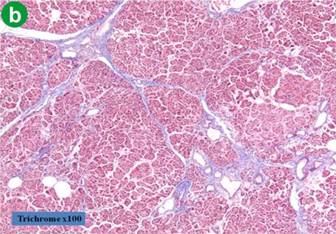

Assessment of Pancreas Consistency

In all cases, pancreatic duct diameter was measured after pancreatic transection by the operator. Parenchyma texture was divided into two groups based upon the extent of fibrotic changes in the resection margin. A fibrotic change was assessed by trichrome staining. Soft pancreatic parenchyma was characterized by the absence of fibrosis or slight thickness of perilobular fibrosis (up to 50 μm). Hard parenchyma was characterized by thick perilobular fibrosis greater than 50 μm (Figure 1).

Figure 1. Results of trichrome staining on the resection margin of the pancreas. a. b. Absence of fibrosis or slight thickness of perilobular fibrosis (less than, or equal to,50 μm ). c. d. Hard parenchyma was characterized by thick perilobular fibrosis greater than 50 μm. The purple color stained by trichrome show the component of fibrotic change in perilobular space. |